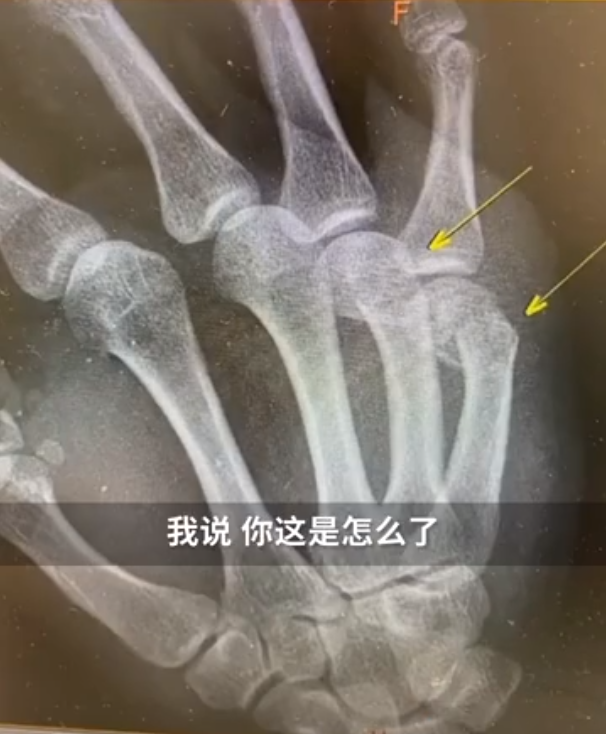

近日,上海新华医院骨科接诊了一男性患者。该患者右手第四第五掌骨肿胀明显。

新华医院骨科主治医师询问后得知,原来这名患者是在家辅导孩子作业时,因孩子作业做得不理想,生气但舍不得打孩子,自己捶墙,没想到把自己捶骨折了。

经过治疗,这位爸爸骨折的手指打了钢板,估计要一段时间不能愉快地工作了。